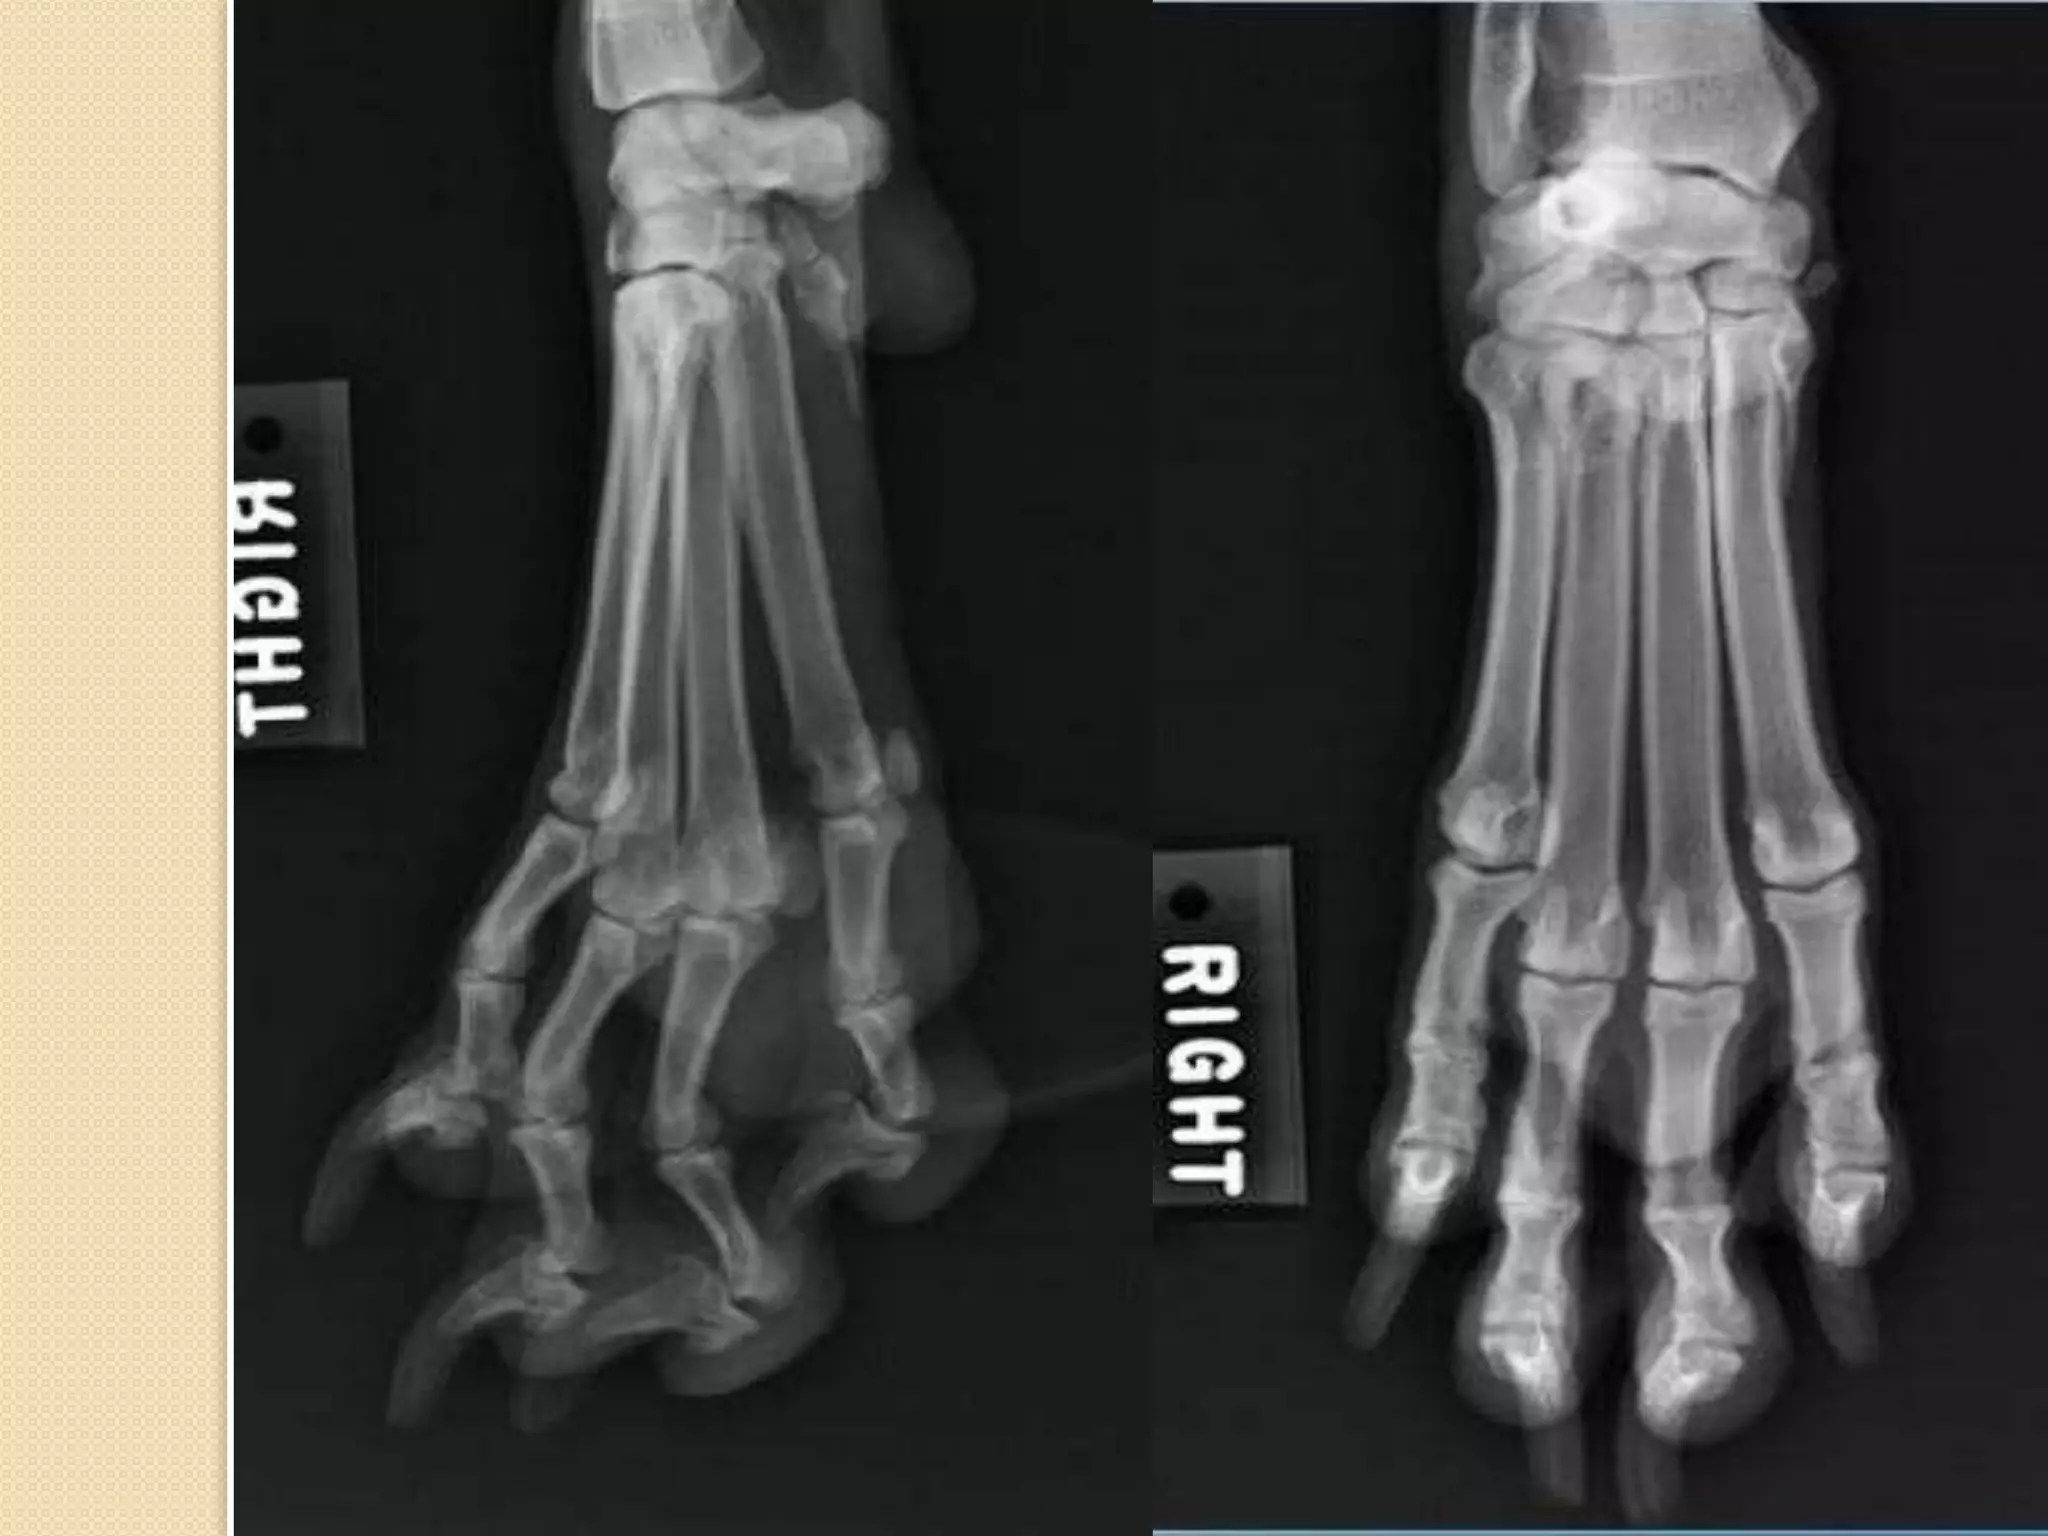

Carpus , metacarpus and

phalanges:

Carpus is a group of small bone which form the

wrist joint , it is arranged in rows which differ

from species to another .

No. of carpal bone : 7

No. of bones in the proximal row : 4

No. of bones in the distal row : 4

Metacarpal bones is a group of long bones

which form the palm in human hand, the number

of these bones differ from species to another.

No. of metacarpal bones : 5

The first one is the shortest while the III and IV is

the longest .

Phalanges is a group of 3 bones which form the

fingers ( except in the first finger 2 bones ) , they

are called 1st , 2nd ,3rd .

The 3rd phalange and the distal part of the 2nd

phalange is coverd by claws.